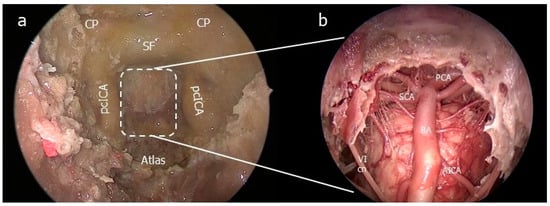

- The petrosal step

4.1. Surgical Anatomy Considerations